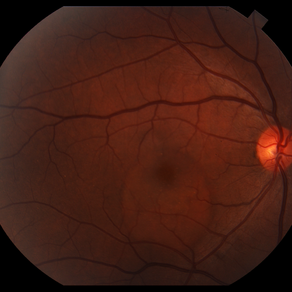

AMPPE

Apr 29 2014 by David W. Faber, MD

24-year-old female presented with central blurry vision for 3-5 days. Vision : OD 20/20, OS 20/100

Photographer: Jodi Schiele, Rocky Mountain Retina Consultants, Salt Lake City, Utah

Condition/keywords: acute multifocal placoid pigment epitheliopathy (AMPPE)